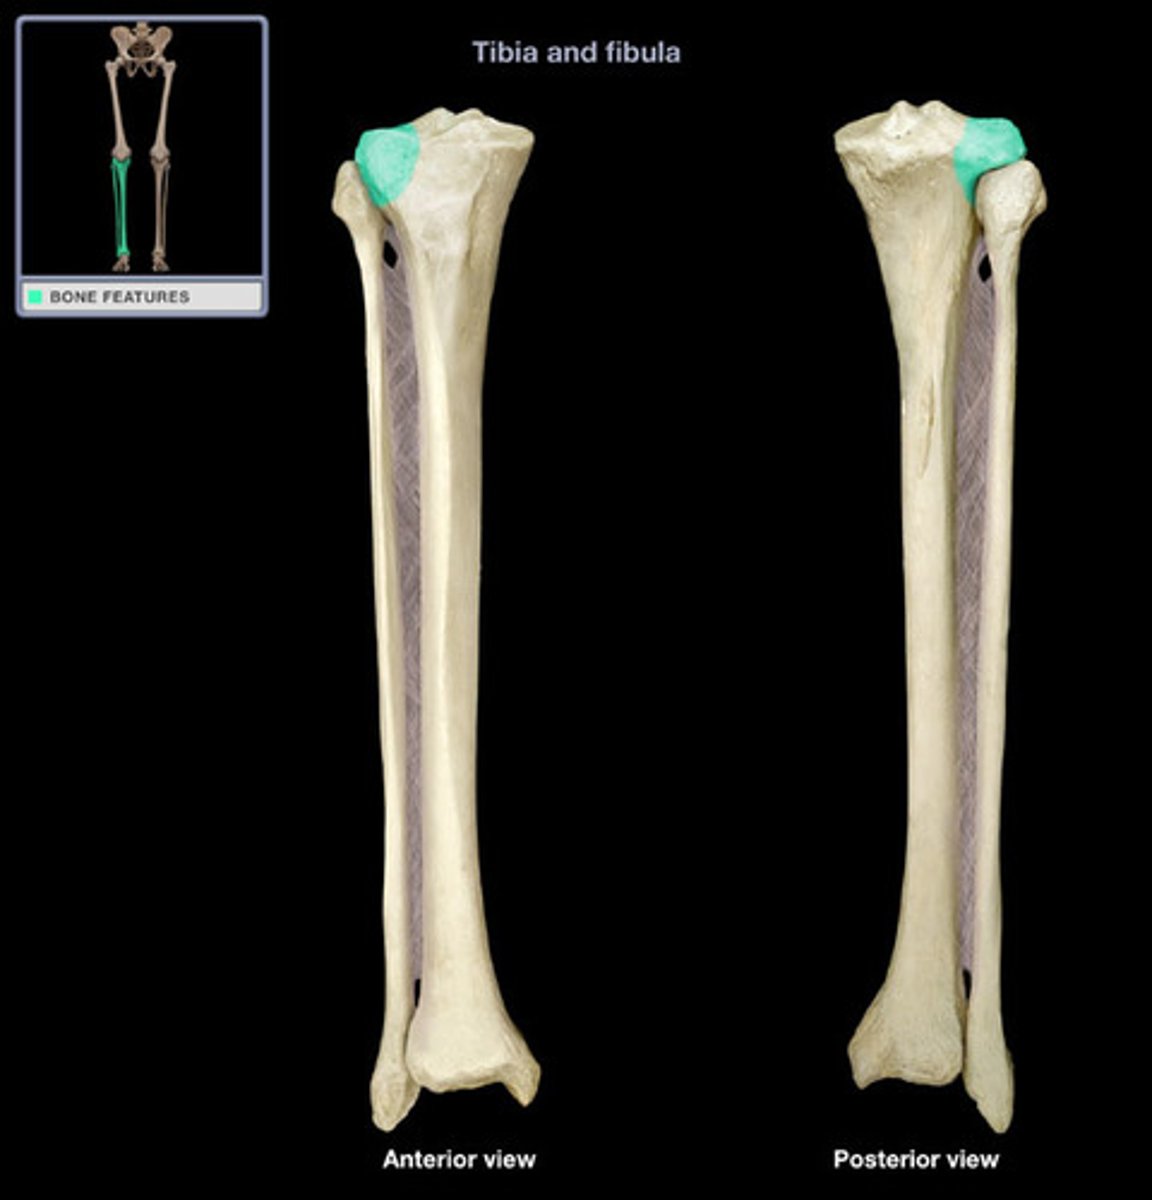

Medial tibial plateau

A

Lateral tibial plateau

B